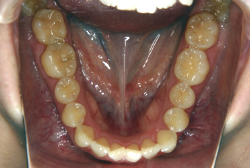

凸凹な歯並びのことを叢生といいます。矯正歯科に来院する患者様の主訴の中で、最も多いのが「配列の凸凹を真っ直ぐにしたい」というものです。歯の大きさと顎の大きさの調和がとれていないことが原因です。

凸凹を主体としたケースの場合、当院の平均治療期間は18ヶ月ですので、このケースは少し長めに経過しました。理由の一つは凸凹の程度がかなり重症だったと言うことですが、もう一つは、右下第2大臼歯が45度くらい前傾していたため、それを整直化させるために時間を要したと考えています。いずれにしても最終結果は大変よい状態と思います。

治療前は並びが乱れて見た目が悪いというのはもちろん問題ですが、歯科医学的に一番困るのは噛み合わせが悪いという点です。上下の犬歯(3番目の歯)は、上下的に離れた位置にあるため接触することができません。つまり歯としては存在していても、歯としては機能していないということです。